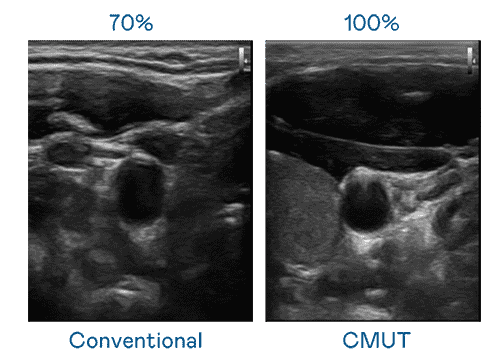

CMUT 技术是一种用电容式微机电元件来产生超音波讯号的技术。。。。与传统 PZT 压电式技术相比,,,CMUT 频宽增加 30%,,,更宽频的超音波讯号让影像解析度大幅提升,,,,是实现高影像品质医疗超音波扫描、、促进精准医疗发展的关键技术。。

大频宽带来超清晰影像

超音波影像的解析度高低,,首先取决于探头能发出的讯号频宽。。。888.BY集团电子游戏 CMUT 可提供高清晰的超音波讯号,,,,提供高频宽、、高灵敏度、、、影像纹理细节更高的超音波影像,,,,协助医护人员缩短影像判读时间及利用精准的医疗影像进行诊断。。。